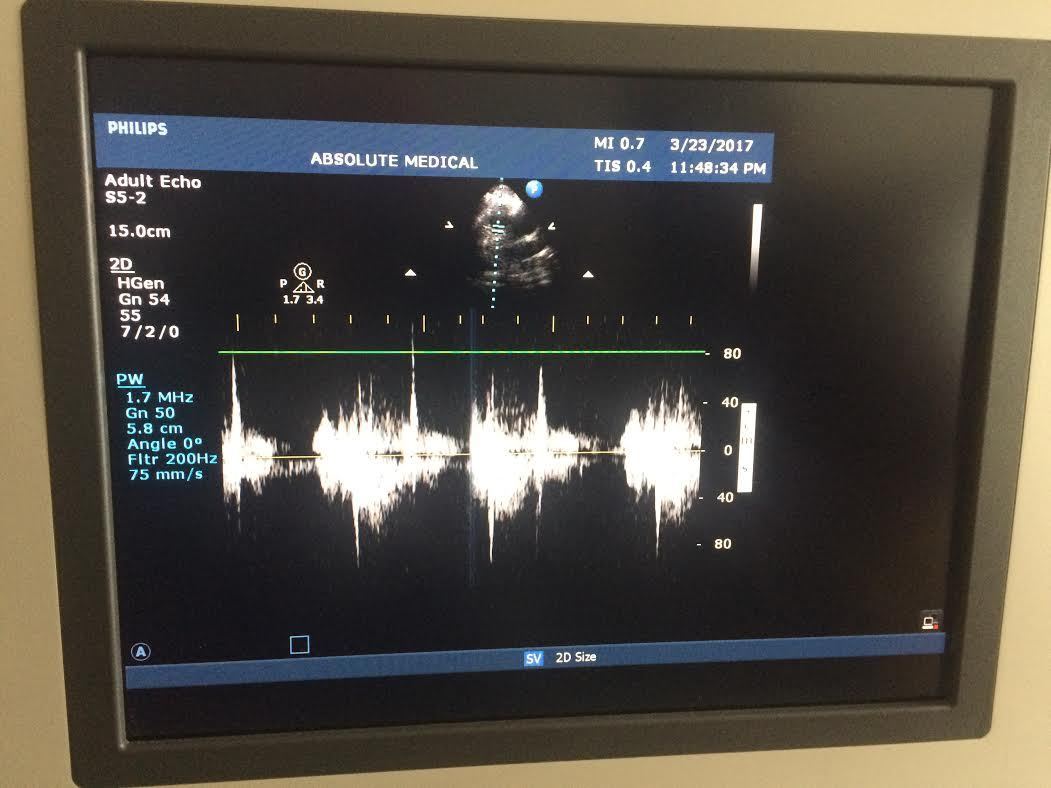

DIAGNOSTIC ULTRASOUND MACHINES FOR SALE